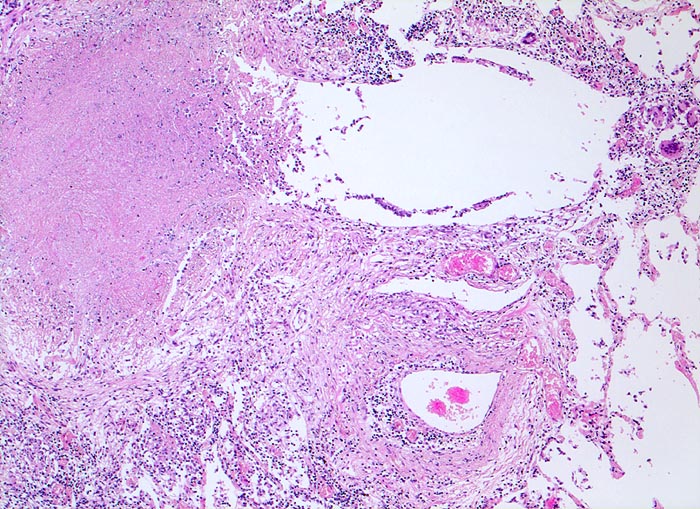

Lungentuberkulose: bronchogene Streuung

Verkäsendes Granulom ausgehend von einem partiell entzündlich zerstörten Bronchiolus. Daneben liegt der dazugehörige Pulmonalarterienast.

Autoptisch wird ein akuter Myokardinfarkt der Vorderwand diagnostiziert. In beiden Lungen fallen oberlappenbetonte knotige weisse, teils kleeblattartige Infiltrate auf und eine subapikal gelegene kleine Kaverne. Einzelne hiläre Lymphknoten der rechten Seite weisen Verkalkungen auf und bilden zusammen mit einem subpleural im Mittellappen gelegenen verkalkten Herd den abgeheilten Primärkomplex. In den käsigen Nekrosen können vereinzelte säurefeste Stäbchen nachgewiesen werden.